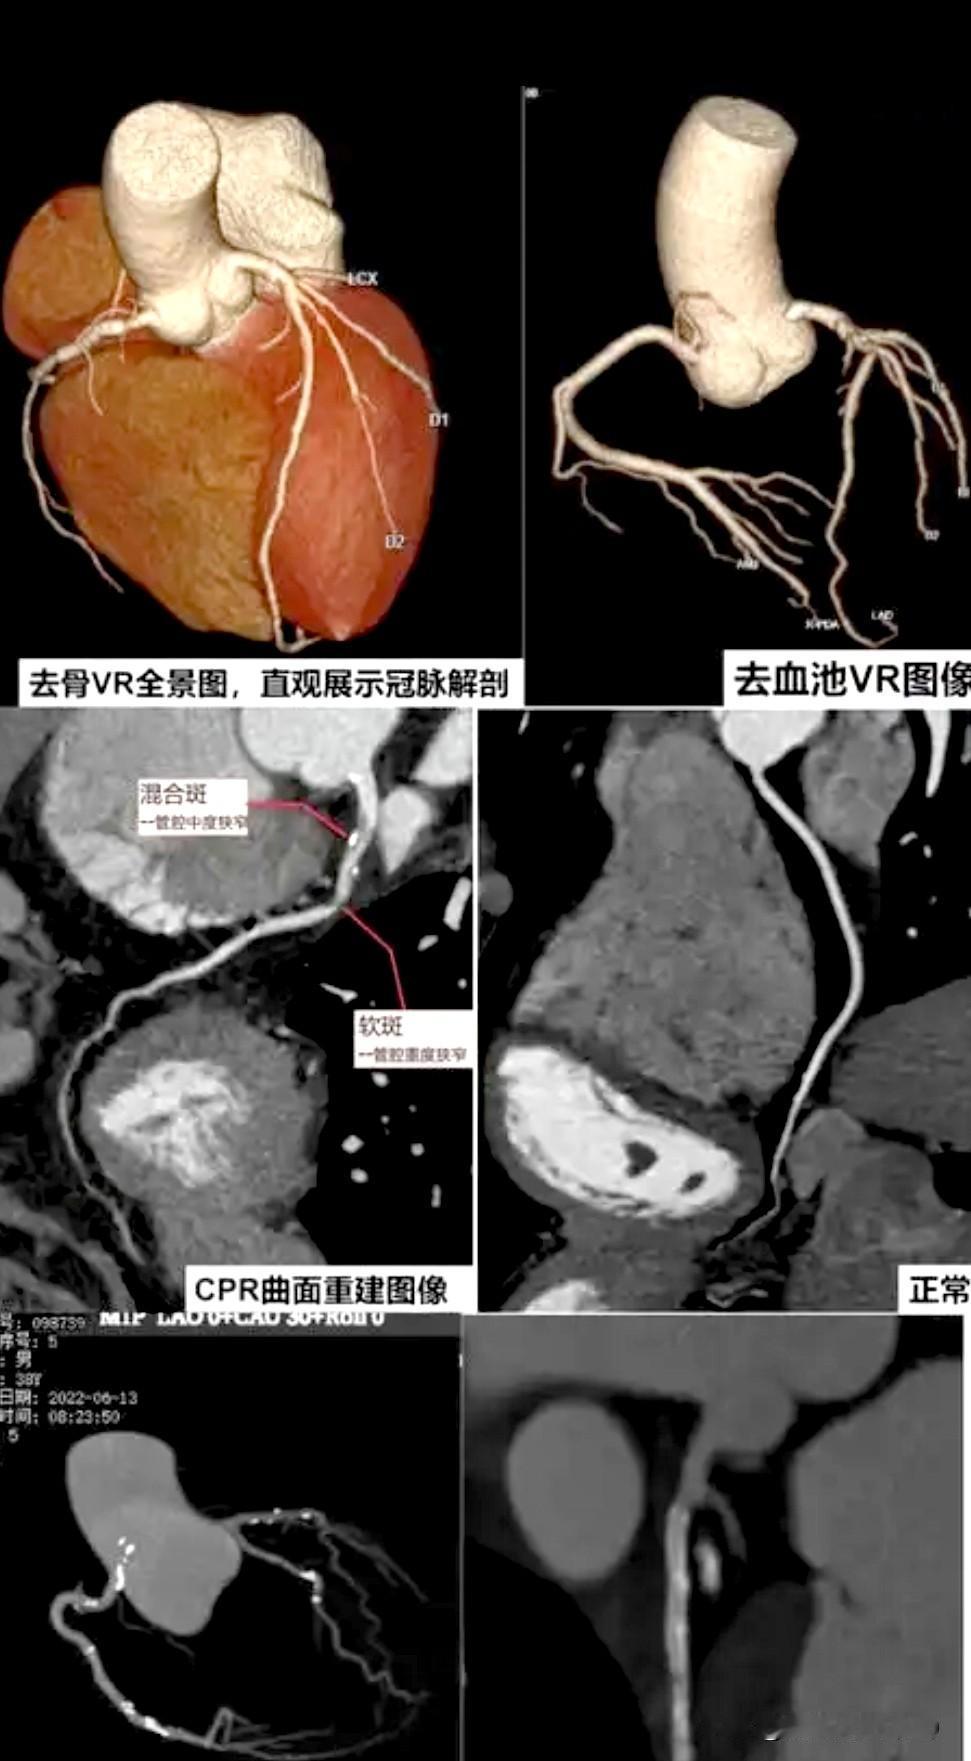

一个选择性体检~冠脉CTA检查,带来的麻烦事! 我们单位福利很好,每年都会会每位员工2000多元的体检,由于体检的人多,医院也给我单位一定的优惠,这样每位员工体检的项目和部位就挺多! 我一个单位同事好朋友,去年体检,发生了一些曲折,他认为我医学知识懂的比较多,于是向我倾诉了他的心事!单位体检有多选项目,他问体检医生,多选项目做什么?医生告诉了他可选择的项目,并问他选择哪项?他倾向于选择冠脉CTA,医生同意,于是做了冠脉CTA,结果显示:心脏冠状动脉前降支有一段有中度狭窄,并有钙化斑块,其余多轻度狭窄,也有些部位钙化斑块! 体检医生通知了他,让他找心血管医生,他特意找了个心血管专家看,这位专家让他吃药,每晚服一片10mg的瑞舒服他汀钙片降血脂,并嘱咐把低密度脂蛋白胆固醇降到1.8mmol/L以下,于是他吃该药一段时间后检查,低密度脂蛋白胆固醇未达1.8mmol/L以下,因此,他又找了另一个专家开依折麦布,继续降低低密度脂蛋白胆固醇,结果这位年纪大一点的专家却极力建议他做冠脉造影,说冠脉CTA不准确,是银标准,冠脉造影才准确,是金标准! 我这位朋友查阅了很多资料,又在网上看了一些医生的视频讲解,说做冠脉CTA有碘过敏、血管损伤可诱发慢性炎症等副作用,不要随便做,还有,我单位也有另一位同事做了冠脉CTA,也有血管中度狭窄,也有医生让他做造影,造影后,结果是示狭窄为轻度,于是不当做冠心病治,让其出院了! 我这位朋友也担心出现冠脉CTA可能误诊夸大狭窄的问题和冠脉造影的副作用,但偶尔也发生静坐沙发左胸闷有一会弊闷不适的感觉,但快走3~6公里,也从未出现不适,经再三思考,并咨询了一些其它医生,他决定不做冠脉造影,而把自已当普通冠心病治,后又每晚吃20mg阿托伐他汀钙片(有医生说,药理试验有明确降低冠心病发作作用,并写入说明书,而瑞舒伐他汀钙片降脂未做过此类试验,于是改服)、10mg依折麦布降血脂,吃了一年,防止冠脉狭窄加重,后期加早晨一片10mg阿司匹林,防止冠脉形成血栓凝集、加一片47.5mg的琥珀酸美托洛尔缓释片,降低心率和心肌缺血症状,吃了也有半年多,期间多次检查血脂,低密度脂蛋白胆固醇均未超过1.8mmol/L,其余指标均未超标,但我这位同事朋友仍很纠结,到底要不要听那位年纪大点的专家建议,做冠脉造影? 思来想去,他把问题发deepseek询问,结果deepseek完全赞成他这个决定,只治疗暂不做冠脉造影,并密切观察症状和医生沟通,还可做运动平板心电图、负荷超声心动图 或 心肌灌注显像,以进一步根据症状反应和心肌是否缺血,辅助判断心肌供血是否存在问题。还建议静息情况心,心闷等症状频繁发作,有劳力性心绞痛症状发作时,再考虑做冠脉造影! 唉,我这位同事朋友感觉看一个病好难,太麻烦、太难选择!医生的分歧还这么大,让病人为了难!还要自己判断该不该做进一步检查,以准确明确病征!太挠头了! 选择性体检项目 冠脉CTA检查